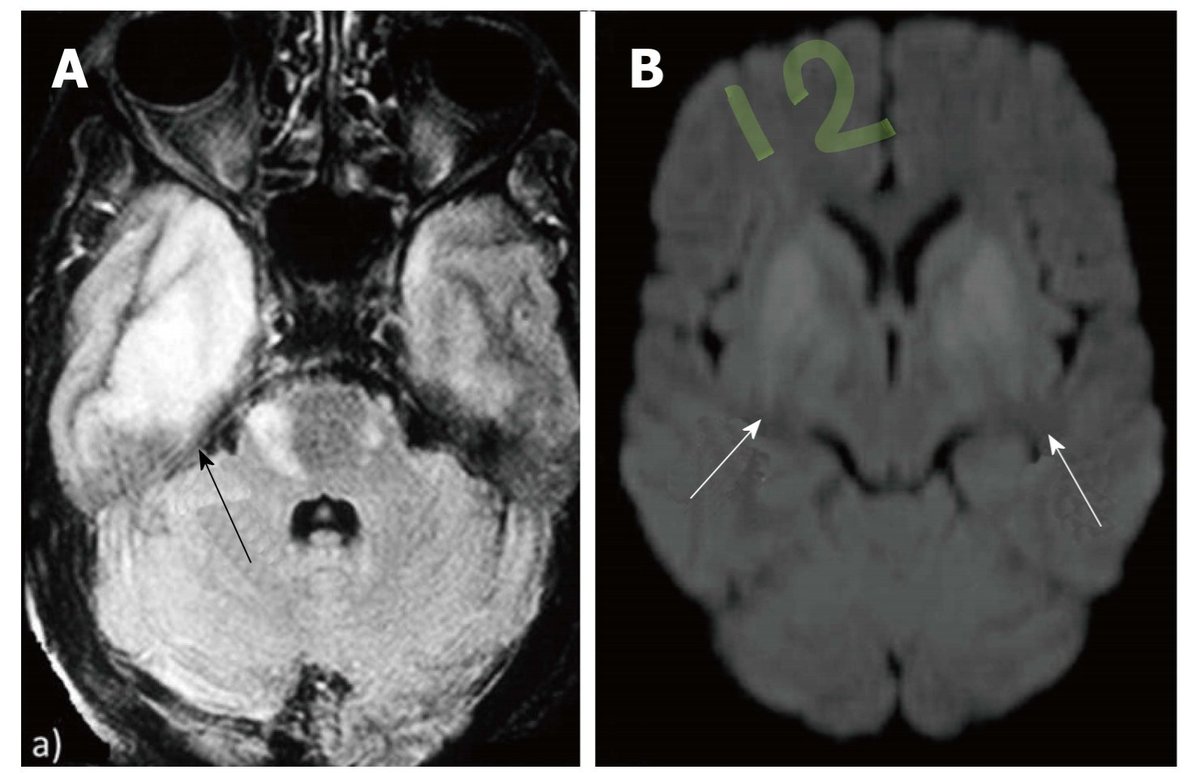

Grey matter hyperintensities:

Infection & infarction showed DWI restriction, whereas infection shows increased perfusion, infarction shows decreased perfusion

Location of lesion highlight etiology, medial temporal >> HSV, Cortex BG & BS >> Japanese virus, pulvinar & BG >> CJD ImageImage